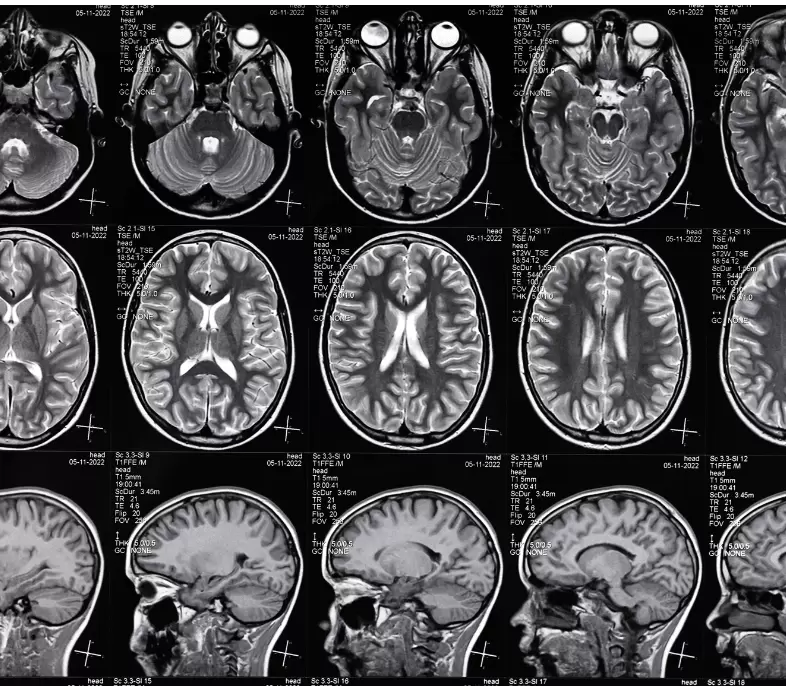

The MD in Radiodiagnosis at Pushpagiri Institute of Medical Sciences & Research Centre is a specialized postgraduate program that provides advanced training in medical imaging techniques for the diagnosis and management of diseases. The course offers extensive hands-on experience in modalities such as X-ray, ultrasound, CT, MRI, and interventional radiology, supported by state-of-the-art imaging equipment and PACS-integrated systems. Under the guidance of experienced radiologists, students develop strong interpretative skills, procedural expertise, and clinical correlation abilities. With a strong focus on academic learning, research, and ethical practice, the program prepares competent and confident radiologists for roles in clinical practice, academics, and advanced imaging specialties.